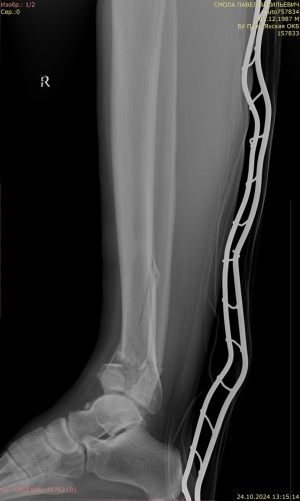

Через 6 дней, после спадения отека, был выполнен открытый накостный остеосинтез большеберцовой кости блокируемыми пластинами (рис. 3).

Рис. 3.